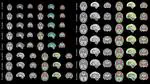

Open source PyTorch implementation of “Dorent, R., Booth, T., Li, W., Sudre, C. H., Kafiabadi, S., Cardoso, J., … & Vercauteren, T. (2020). Learning joint segmentation of tissues and brain lesions from task-specific hetero-modal domain-shifted datasets. Medical Image Analysis, 67, 101862 (📖).”

NiftyMIC is a Python-based open-source toolkit for research developed within the GIFT-Surg project to reconstruct an isotropic, high-resolution volume from multiple, possibly motion-corrupted, stacks of low-resolution 2D slices. Read “Ebner, M., Wang, G., Li, W., Aertsen, M., Patel, P. A., Aughwane, R., … & David, A. L. (2020). An automated framework for localization, segmentation and super-resolution reconstruction of fetal brain MRI. NeuroImage, 206, 116324 (📖).”